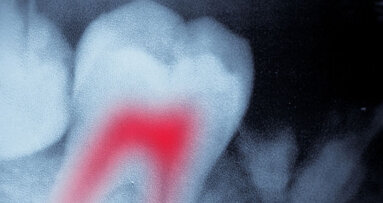

L’examen radiographique a montré l’espace marginal autour de l’amalgame, en particulier du côté mésial (Fig. 1). Le traitement endodontique était incomplet : la préparation des canaux radiculaires était inadéquate, et la longueur de travail ainsi que le scellement dans les trois dimensions étaient insuffisants. Un canal de la racine distale semblait n’avoir subi aucun traitement. Une morphologie radiculaire irrégulière compatible avec une hypercémentose était visible dans la moitié apicale des racines de la dent 46, dont le volume était accru et de forme ronde. On pouvait également observer un élargissement de l’espace parodontal sur presque toute son étendue. La radiographie montrait une lésion radiculaire importante sur la racine distale et une autre, de taille plus petite, sur la racine mésiale.

Fig. 1: Radiographie de la situation préopératoire montrant un traitement endodontique insuffisant de la dent 46. Des micropercolations de la restauration en amalgame de la couronne ont en outre été détectées. Les deux racines présentaient également des lésions apicales évidentes. Les deux dents adjacentes avaient migré vers la dent 46 et fermé les espaces interproximaux.